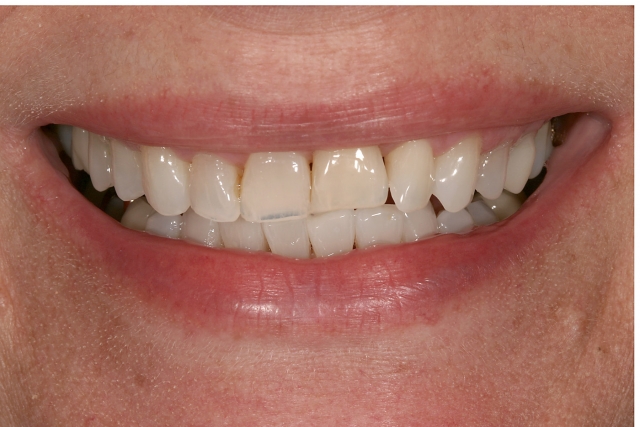

If the patient has a low smile line — or the gingival margin position is still correct and the rate of resorption is slow — keeping and restoring the ankylosed tooth in its current position is a simple way to improve the esthetics. The unknown of this treatment option, though, is how long the tooth will last before the resorption advances to the point the tooth structurally needs to be extracted. Even though there is a significant gingival margin discrepancy on the ankylosed tooth #9, the impact on the overall esthetics is low because of the patient’s low smile. (Figure 3)

Given that the resorption is occurring at slow rate — the tooth became ankylosed before the completion of growth and the patient is now in her late 50s — the treatment plan was just to restore the incisal edges of #8, #9 and #10 with composite. The composite restorations were in place approximately 10 years before the resorption advanced to the point that #9 required extraction (Figure 4).